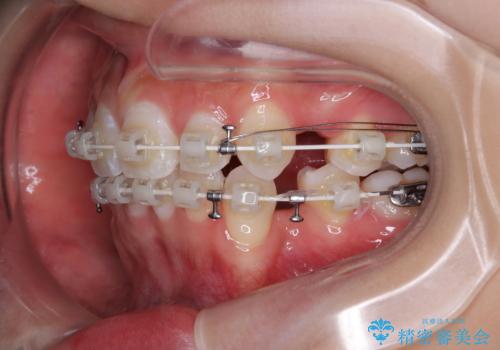

- 矯正装置

- 審美装置

- 口を閉じたときに飛び出してしまう上顎前歯を気にして来院された患者様です。

下顎はデコボコが気になっていたため、上下左右第一小臼歯4本を抜去して、ワイヤー装置にて口元の突出感を改善するよう矯正治療を行うこととしました。

下唇に前歯が当たって跡が残ってしまう状態でしたが、スッキリとした口元に仕上げることができました。